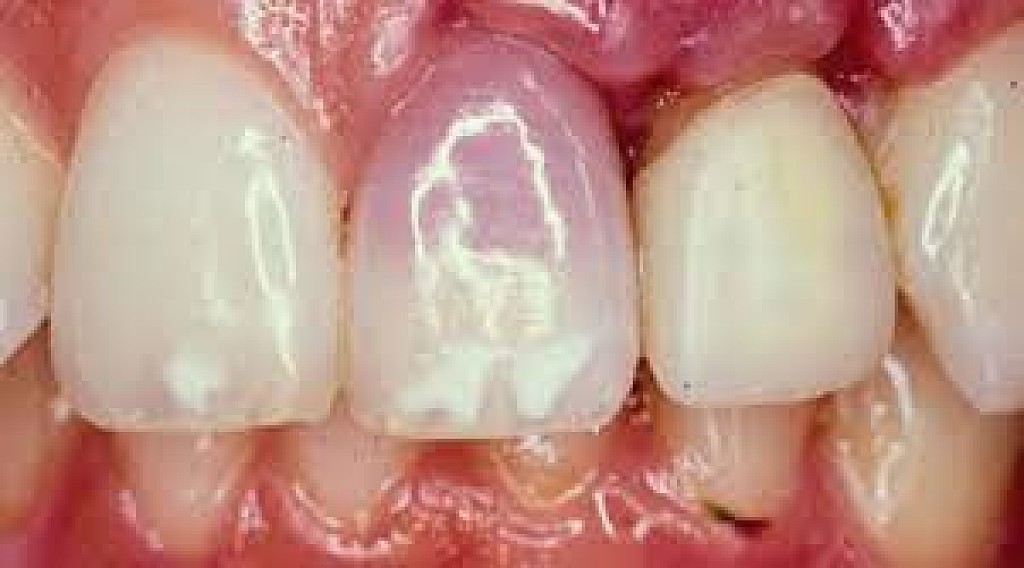

The death of a tooth

When a tooth dies, the blood supply – which gives the tooth its natural, healthy color – will stop. Because the tooth is not receiving the nutrients it needs, it will begin to necrotise, darken, die and slowly go black.

Will my tooth go black after root canal?

A common misconception is that a tooth will go black after a root canal treatment. Teeth will often go black before root canal treatment as the tooth rots and decomposes on the inside. If root canal treatment is done well, all of the decomposing tissue will be removed and the blackness will not get worse. There may, however, be some mild darkening of the tooth after a root canal, depending on exactly how the root canal treatment is done and with which material.

How long does it take for a tooth to go black?

If the cause of the blackness is due to tooth decay, the blackness can happen over a period of years. If the cause of the blackness is due to trauma, as soon as the blood supply has been cut off from the tooth, the internal tooth tissue will begin to die and turn black.

Will a dead tooth go black?

If a dead tooth is left untreated, it will go black as the internal tooth tissue dies and decomposes. If the dead tooth has been root treated with a tooth-colored treatment, the tooth may not go completely black, although it may darken slightly.